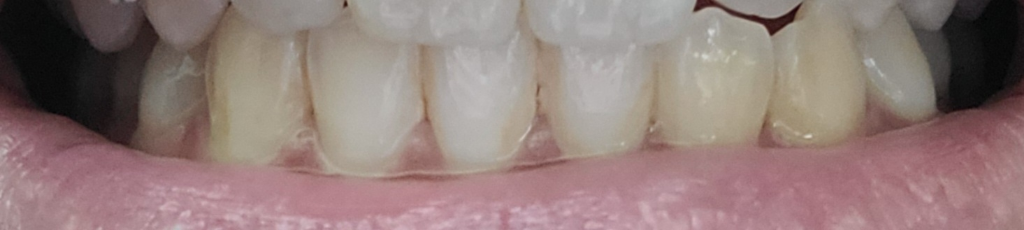

식사를 하거나 일상생활에서 교합을 하는데 큰 문제가 없다면 정상교합으로 판단합니다.

피개량이 적긴하지만 위에 치아가 아래 치아를 덮고 있다면 반대교합이나 절단교합이 아닌 정상교합의 범주에 있다고 판단을 하게 됩니다.